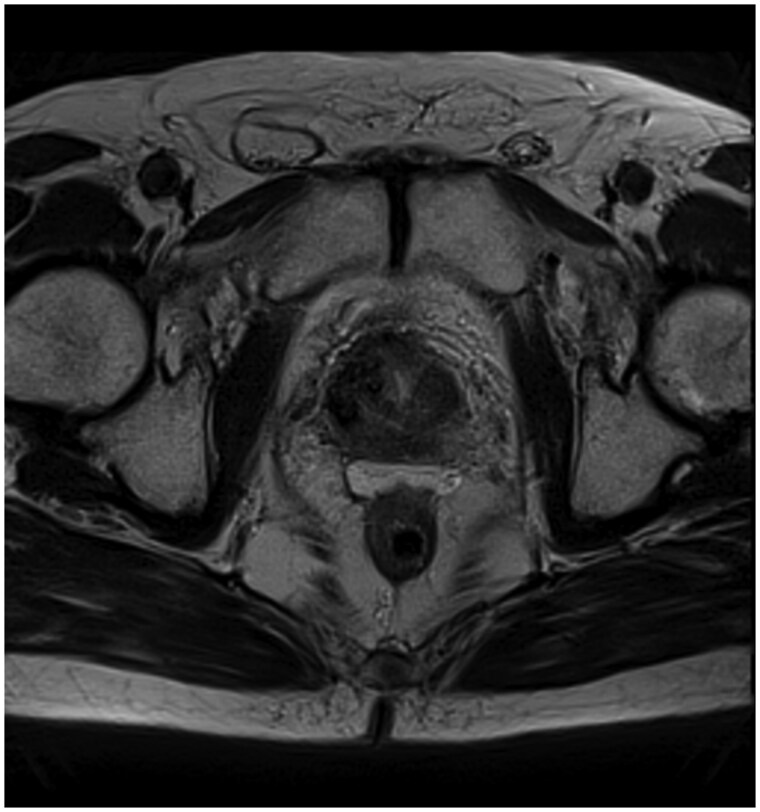

有盆腔放射史的前列腺癌患者的放射治疗可能受到直肠剂量限制和直肠毒性风险的限制。直肠间隔剂已被证明可以改善前列腺癌治疗中的直肠剂量学。本研究旨在评估先前接受过放射治疗的前列腺癌患者在直肠和前列腺之间放置水凝胶间隔物(特别是SpaceOAR)的安全性和结果。在这个回顾性的病例系列中,我们分析了8例连续接受盆腔放疗或盆腔放疗的患者的医疗记录,这些患者接受过经会阴SpaceOAR安置。我们记录了SpaceOAR放置后、放疗前后的并发症发生率。在这个患者队列中有一系列的并发症,从盆腔疼痛到更严重的并发症,如直肠穿孔、脓肿和瘘管。8例患者中2例出现严重并发症。再照射可能增加正常组织并发症的风险;然而,在一小部分患者中,使用SpaceOAR放置水凝胶垫片治疗既往盆腔放疗的前列腺癌患者,其直肠并发症的发生率高于预期。我们强烈建议在此患者组中谨慎使用SpaceOAR。

Treating prostate cancer with radiation therapy in patients with a history of prior pelvic radiation may be limited by rectal dose constraints and the risk of rectal toxicity. Rectal spacers have been shown to improve rectal dosimetry in the treatment of prostate cancer. This study aimed to evaluate the safety and outcomes of hydrogel spacer placement, specifically SpaceOAR, between the rectum and prostate in prostate cancer patients who had previously undergone radiation therapy. In this retrospective case series, we analysed the medical records of 8 sequential patients undergoing reirradiation in the setting or prior pelvic radiation, who had received transperineal SpaceOAR placement. We documented the incidence of complications after SpaceOAR placement, before and after undergoing radiation therapy. There was a spectrum of complications in this patient cohort, ranging from pelvic pain to more severe complications such as rectal perforation abscess and fistula. Severe complications occurred in 2 of the 8 patients. Re-irradiation may increase the risk of normal tissue complications; however, hydrogel spacer placement using SpaceOAR in prostate cancer patients with prior pelvic radiation was associated with a higher rate of rectal complications than expected in a small series of patients. We urge caution when using SpaceOAR in this patient group.